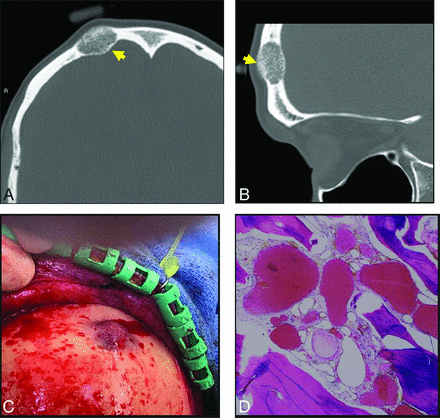

Axial T1 (A) and axial T1 C+ FS (B) images through the maxilla demonstrate a T1-intermediate, heterogeneously enhancing expansile lesion centered in the right maxillary alveolus (yellow arrow, A and B). The lesion extends beyond the cortical margin, and there is poor identification of the normal cortex. Axial T2 (C) and axial T2 FS (D) sequences demonstrate that the lesion is T2-hyperintense with internal T2-hypointense trabeculae (yellow arrows, C and D). The diagnosis of IOVM was confirmed on pathology. C+ indicates with contrast.